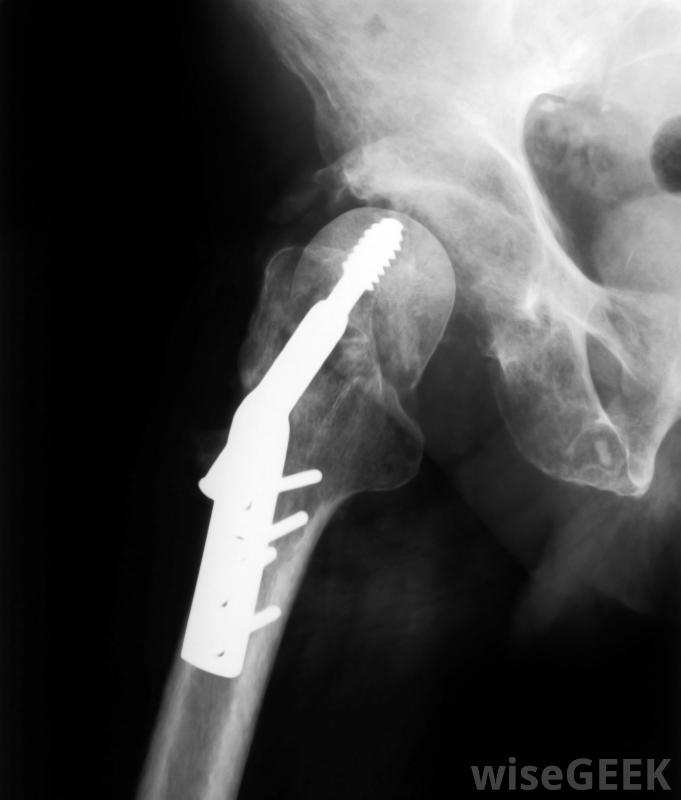

20世紀60年代,無血手術最初被定義為不使用輸血。然而,這個簡單的定義并沒有被接受為對無血手術的完整描述,這就是為什么一些個人和組織在最初的定義基礎上進行了擴展。對無血手術的更徹底的定義包括完全避免輸血或血液制品的要求。重點在于避免輸血和避免使用血液制品。可以使用高度先進的外科手術程序和技術來消除使用輸血或血液制品的需要髖關節修復和置換手術通常不需要輸血首先包括單純的愿望和企圖排除使用輸血,第二個絕對需要這樣的排除。這就是為什么并非所有的無血手術都是真正的無血的。這一說法是指在手術或其他醫療程序中避免使用輸血或血液制品的可能失敗的嘗試。醫療程序和實際的手術都可以是無血的,因此可以這樣說盡管有許多預防措施來預防問題,但大多數人還是寧愿避免輸血人們避免輸血或使用血液制品是有充分理由的。各種形式的肝炎和人類免疫缺陷病毒(HIV)等疾病可能是通過使用輸血或血液制品而感染的有助于防止這種傳播,并不能保證病人不會接受受污染的血液。持宗教觀點反對獻血和接受血液的人也屬于對無血手術和醫療程序感興趣的人可以進行的無輸血手術包括髖關節和膝關節置換術和心臟直視手術。有時也可以選擇使用通常被認為是安全的血液和血液制品的替代品,如生理鹽水和乳酸林格他們接受無血手術,即所謂的"無血醫學指令"。他們也可以通過另一個稱為"預先醫療指令"的法律文件來告知他們拒絕使用血液或血液制品。這樣的文件是關于醫療護理的指示,法律要求醫療保健提供者尊重并遵守這一原則。

心臟直視手術是一種無需輸血即可完成的手術。